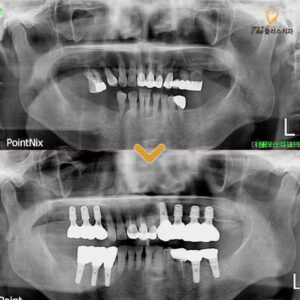

울산치과 상실된 공간을 회복하기 위해서는

울산치과 상실된 공간을 회복하기 위해서는 치아는 우리가 일상생활을 영위하는 데 있어 매우 중요한 역할을 하고 있는데요. ​ 사람마다 치아 한 개를 잃는다는 것은 일상에서 생각보다 큰 변화를 불러올 수 있습니다. ​ 음식을 저작할 때 한쪽으로만 집중하게 되면 근육과 관절에 부담이 더보기…